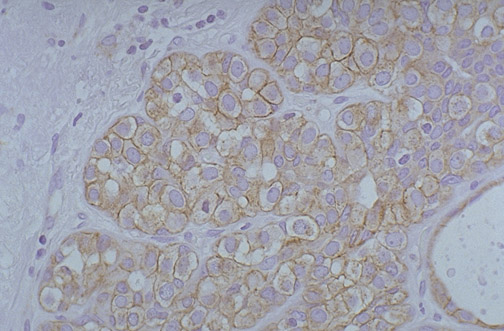

There is weak perimembranous staining for HER2-neu (C-erb B2), with a score of 2+, classified as positive, for this breast carcinoma.